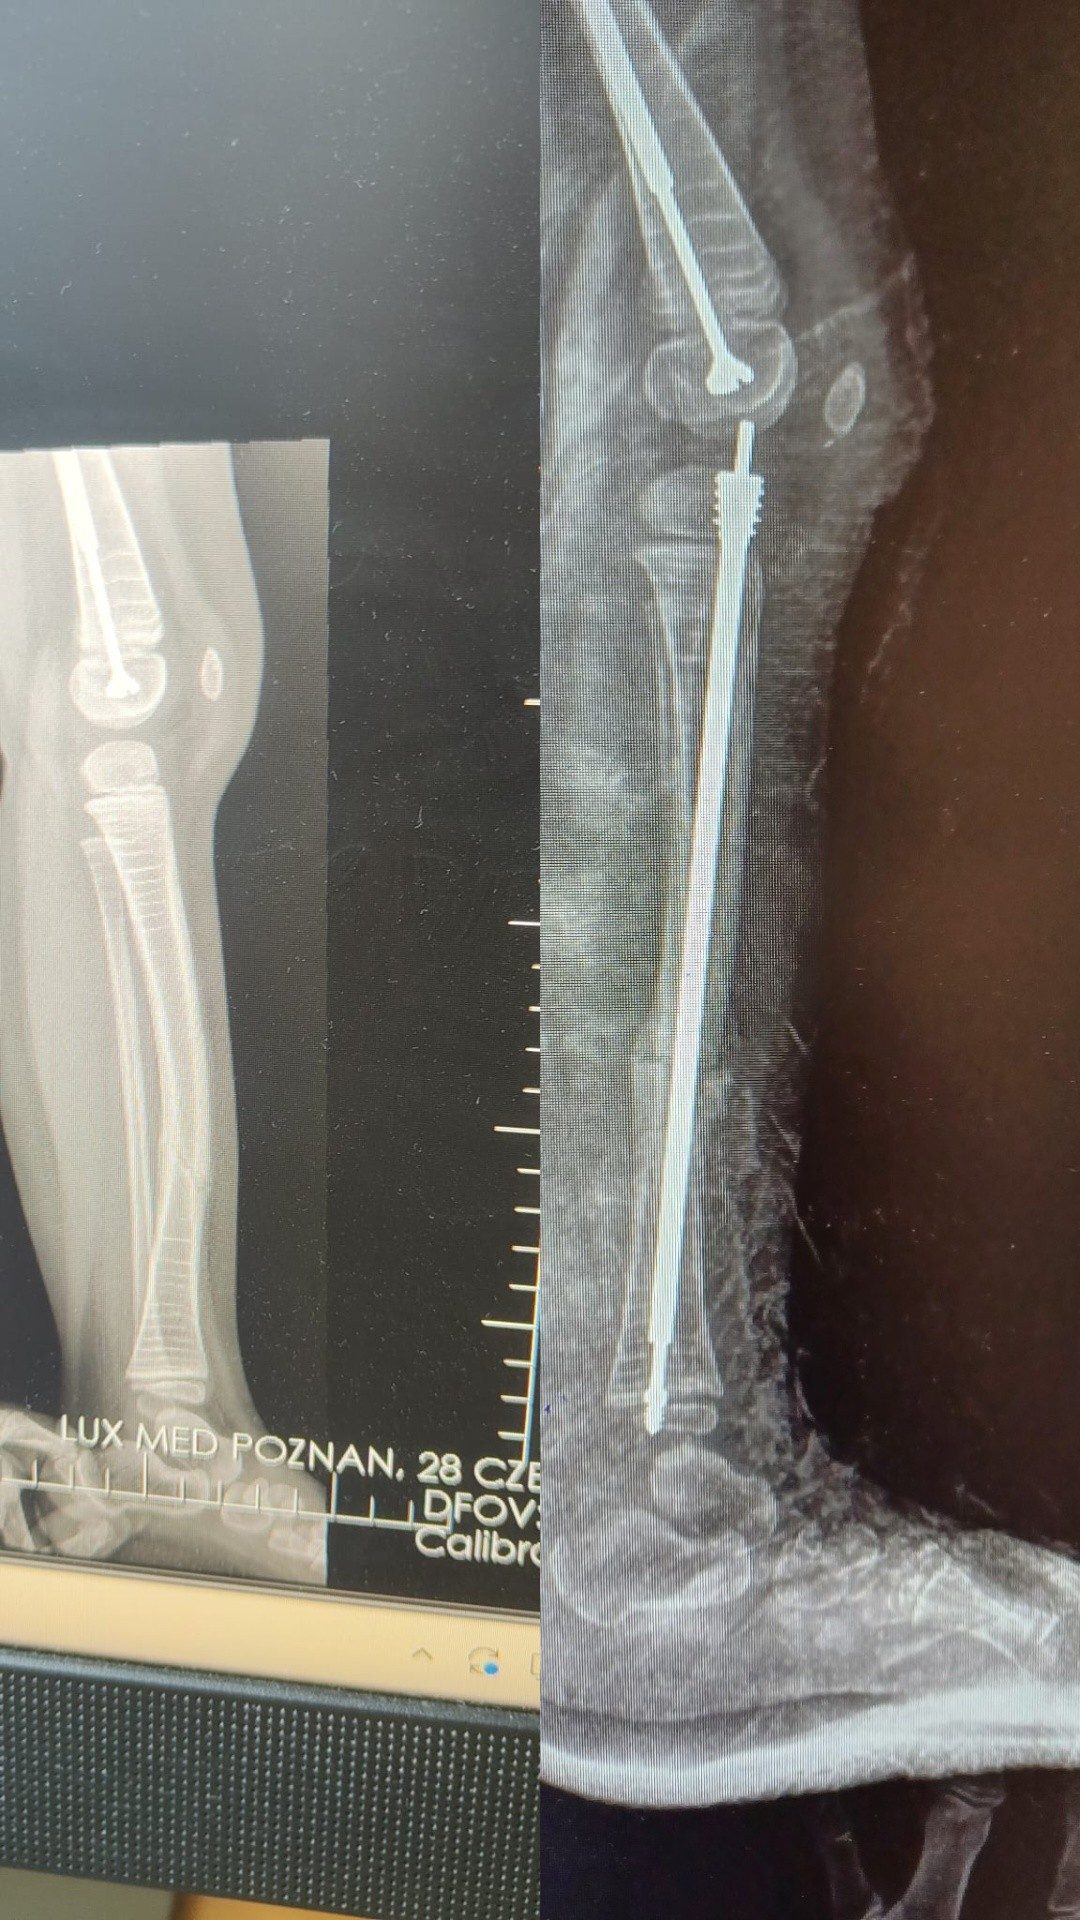

Nazywam się Zosia Sieja i od pierwszych dni mojego życia zmagam się z Wrodzoną Łamliwością Kości. Jestem taka malutka, a przeszłam już 17 złamań kości. Moje dzieciństwo okraszone jest bólem i niepokojem, ale mimo to dzięki moim najbliższym i Wam-Kochani Darczyńcy, nie poddaję się i każdego dnia walczę, dzielnie stawiając czoła chorobie.

W celu wzmocnienia moich kości przeszłam zabiegi operacyjne polegające na wstawieniu prętów stabilizujących. Niebawem czeka mnie następna operacja wstawienia kolejnych prętów stabilizujących moje kości. Dodatkowo codziennie wykonuję ćwiczenia i rehabilituję się, aby zapobiegać złamaniom i wzmacniać kości.